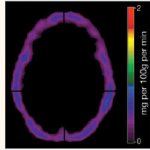

• PET/CT of the heart.

Functional load tests are widely used.

They are used, among other things, to detect the early stages of coronary artery disease or a painless form of the pathology, when the disorders cannot be determined at rest. Walking, climbing stairs, exercises on exercise machines (an exercise bike, a treadmill), accompanied by ECG recording of current indicators, are used as stress tests for suspected coronary heart disease. The standard and most accurate method for this is diagnostics using a treadmill (treadmill) and an exercise bike (bicycle ergometry). Positron emission tomography (PET) is used to diagnose viable cardiac muscle cells. Radiopharmaceuticals are used, the accumulation of which in heart cells reveals viable and necrotic areas.